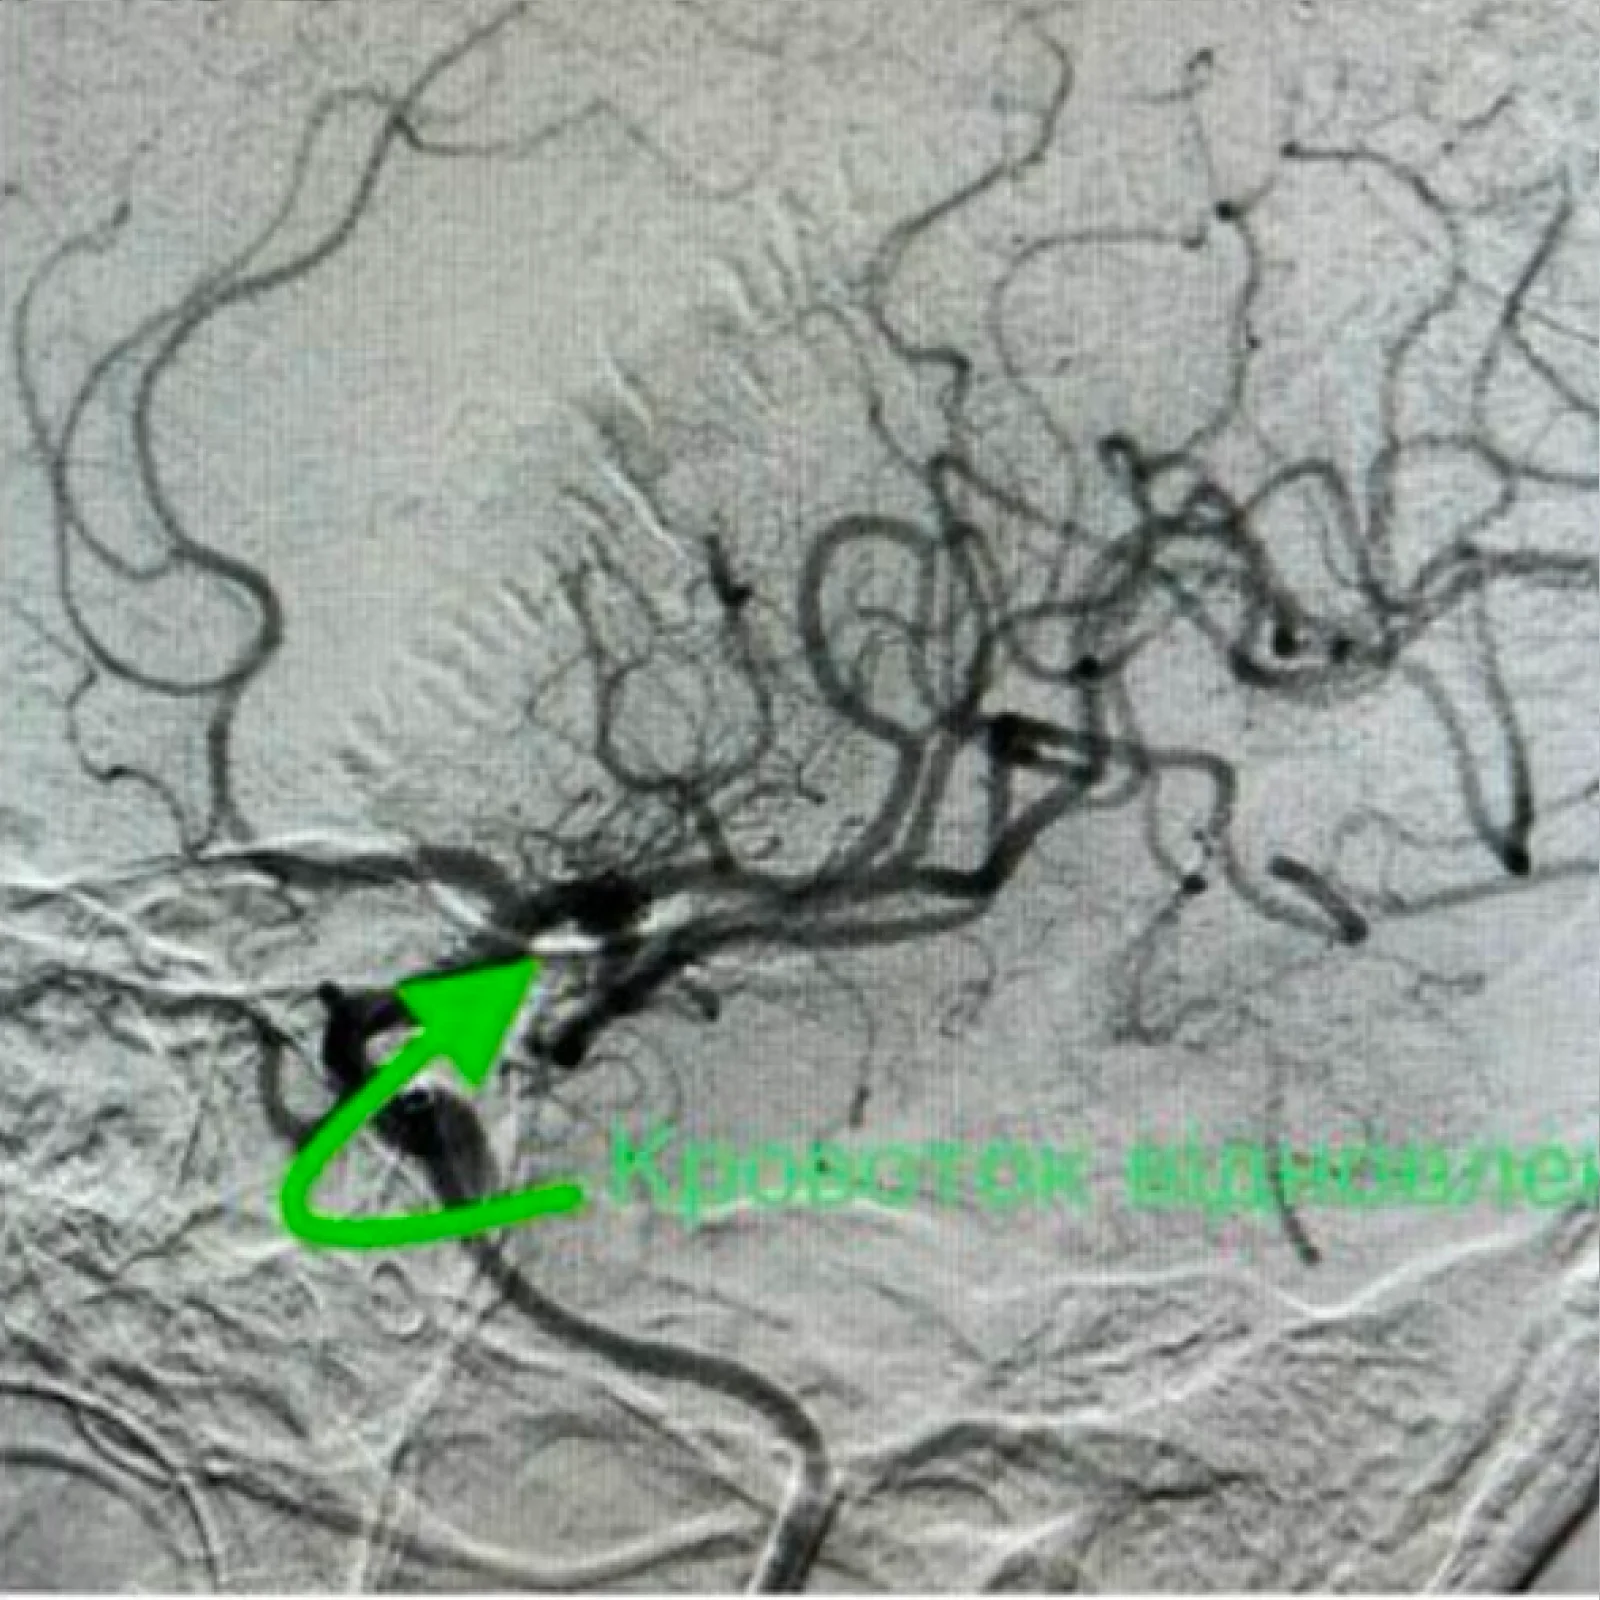

Селективна субтракційна ангіографія (DSA, Digital Subtraction Angiography) — це сучасний метод візуалізації судин, який дозволяє отримати чіткі зображення артерій і вен без “зашумлення” від навколишніх тканин.

Процедура проводиться за допомогою контрастного введення через катетер в конкретну судину, а спеціальна технологія субтракції “віднімає” фонові структури, залишаючи лише кровоносні судини на зображенні.

• Тромбектомія та тромболізис

• Механічне або медикаментозне видалення тромбів при гострих оклюзіях судин

• Механічна тромбектомія при ішемічному інсульті